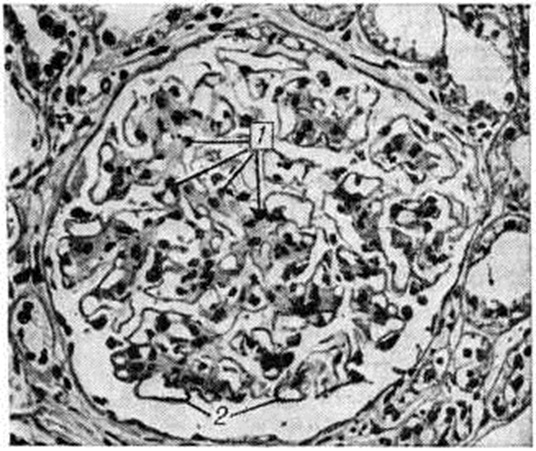

Гломерулосклероз диабетическийГломерулосклероз диабетический (латинское glomerulus клубочек + склероз; греческий diabetes, от diabainein проходить; синонимы: интеркапиллярный гломерулосклероз, синдром Киммелстила — Уилсона) — специфическая и наиболее частая форма поражения почек при сахарном диабете; впервые описана в 1936 году. Гломерулосклероз диабетический является одним из наиболее тяжёлых осложнений сахарного диабета (смотри полный свод знаний Диабет сахарный). Частота Гломерулосклероз диабетический по материалам аутопсии колеблется от 19,5% [Хендерсон (L. Henderson)] до 50,9% [Уайт (White)] у больных, страдающих сахарным диабетом свыше 20 лет. В клинике Гломерулосклероз диабетический, по данным Р. А. Хейфец и Л. И. Каминской, выявляется в 6%, по данным Э. Глоссит Москович — в 17,8% и даже в 48% случаев (В. В. Сура) от числа больных, страдающих сахарным диабетом. У женщин, страдающих сахарным диабетом, Гломерулосклероз диабетический встречается в 30%, у мужчин — в 19,5% случаев. Патологическая анатомияГистологические изменения почек при Гломерулосклероз диабетический весьма полиморфны; выделены три основных формы поражения — узелковая, диффузная и экссудативная. Некоторые авторы вместо экссудативной выделяют смешанную форму. Узелковая форма характеризуется наличием в клубочках эозинофильных образований (узелков) округлой или овальной формы (рисунок 1), содержащих вакуоли. Они могут занимать часть или весь клубочек, по периферии которого в последнем случае располагаются сохранившиеся сдавленные капиллярные петли. Одновременно наблюдается расширение и аневризмы капилляров клубочков, утолщение их базальных мембран. При гистохимическом исследовании узелков они вначале окрашиваются как фибрин, а в дальнейшем как коллаген. Узелки содержат большое количество высокомолекулярных мукополисахаридов, небольшое количество кислых мукополисахаридов, жировых субстанций, в основном ненасыщенных жирных кислот и холестеринэстеров. При электронно-микроскопическом исследовании видно, что формирование узелков происходит в мезангии в виде скопления в нем глыбок и трабекул, сходных с веществом базальной мембраны. Диффузная форма выражается в однородном расширении и уплотнении мезангия с вовлечением в процесс базальных мембран капилляров, которые резко утолщены. Образующиеся в мезангии мембраноподобные структуры не сливаются в сплошные массы, и образования узелков не происходит. Базальные мембраны капиллярных петель клубочков утолщены, структура их исчезает (рисунок 2). Смешанная форма характеризуется сочетанием типичных узелков с диффузным уплотнением мезангия и утолщением базальных мембран капилляров клубочков (рисунок 3). По данным электронно-микроскопических исследований утолщение базальных мембран капилляров клубочков возникает рано, нередко до появления каких-либо клинических проявлений поражения почек, и имеет место, видимо, при всех формах Гломерулосклероз диабетический Утолщение мембран наблюдается не только у больных, но и у молодых людей из диабетически отягощённых семей. Экссудативная форма встречается реже, чем предыдущие, и характеризуется прежде всего так называемый «фибриноидными шапочками», которые представляют собой отложения PAS-положительного материала между эндотелием и базальной мембраной капилляров (рисунок 4). При иммуногистохимическом исследовании в этих образованиях обнаруживается значительное количество комплементсвязывающих иммуноглобулинов, что даёт основание считать их комплексом антиген—антитело, а не сывороточным экссудатом. «Фибриноидные шапочки» не являются специфическими для Гломерулосклероз диабетический, но вместе с тем они обнаруживаются при тяжёлых и быстро прогрессирующих его формах. С ними часто сочетаются так называемый «капсульные капли», располагающиеся на внутренней стороне боуменовой капсулы. |